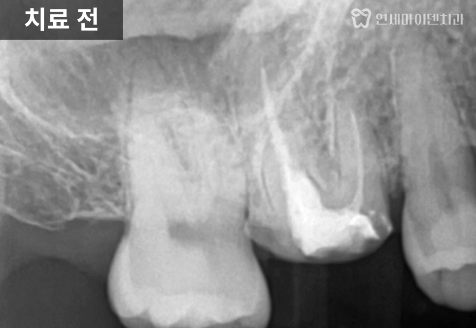

임시 재료를 제거하고 내부를 확인해 보니

거타퍼차(GP)라는 신경치료

마무리 재료가 채워져 있었습니다.

원래 신경치료 마무리 재료는

신경관에서 끝나야합니다.

위쪽에는 전부 제대로 접착을 해서

레진코어를 통해 크라운을 해야합니다.

하지만 그렇지않았기때문에

부러진 것으로 보입니다.